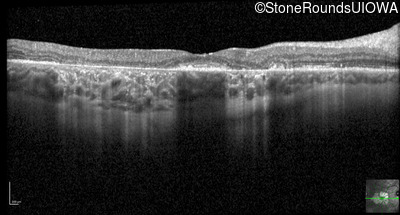

Optical Coherence Tomography - Left - 20/125 -2

Exemplar / OCT Stack

OCT Stack